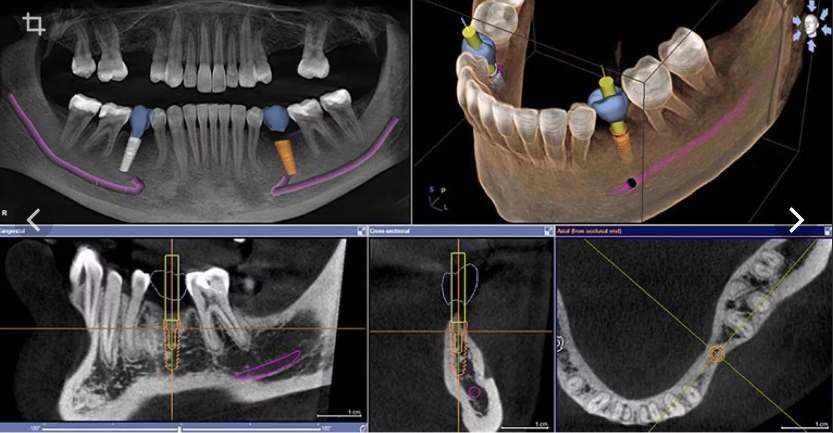

Этот курс был разработан специально для стоматологов, которые хотят уверенно работать с цифровыми технологиями. За 3 вебинара вы пройдёте путь от основ навигации и моделирования шаблонов до планирования тотальных реабилитаций и разбора хирургического протокола с клиническими примерами.

Этот курс был разработан специально для стоматологов, которые хотят уверенно работать с цифровыми технологиями. За 3 вебинара вы пройдёте путь от основ навигации и моделирования шаблонов до планирования тотальных реабилитаций и разбора хирургического протокола с клиническими примерами.